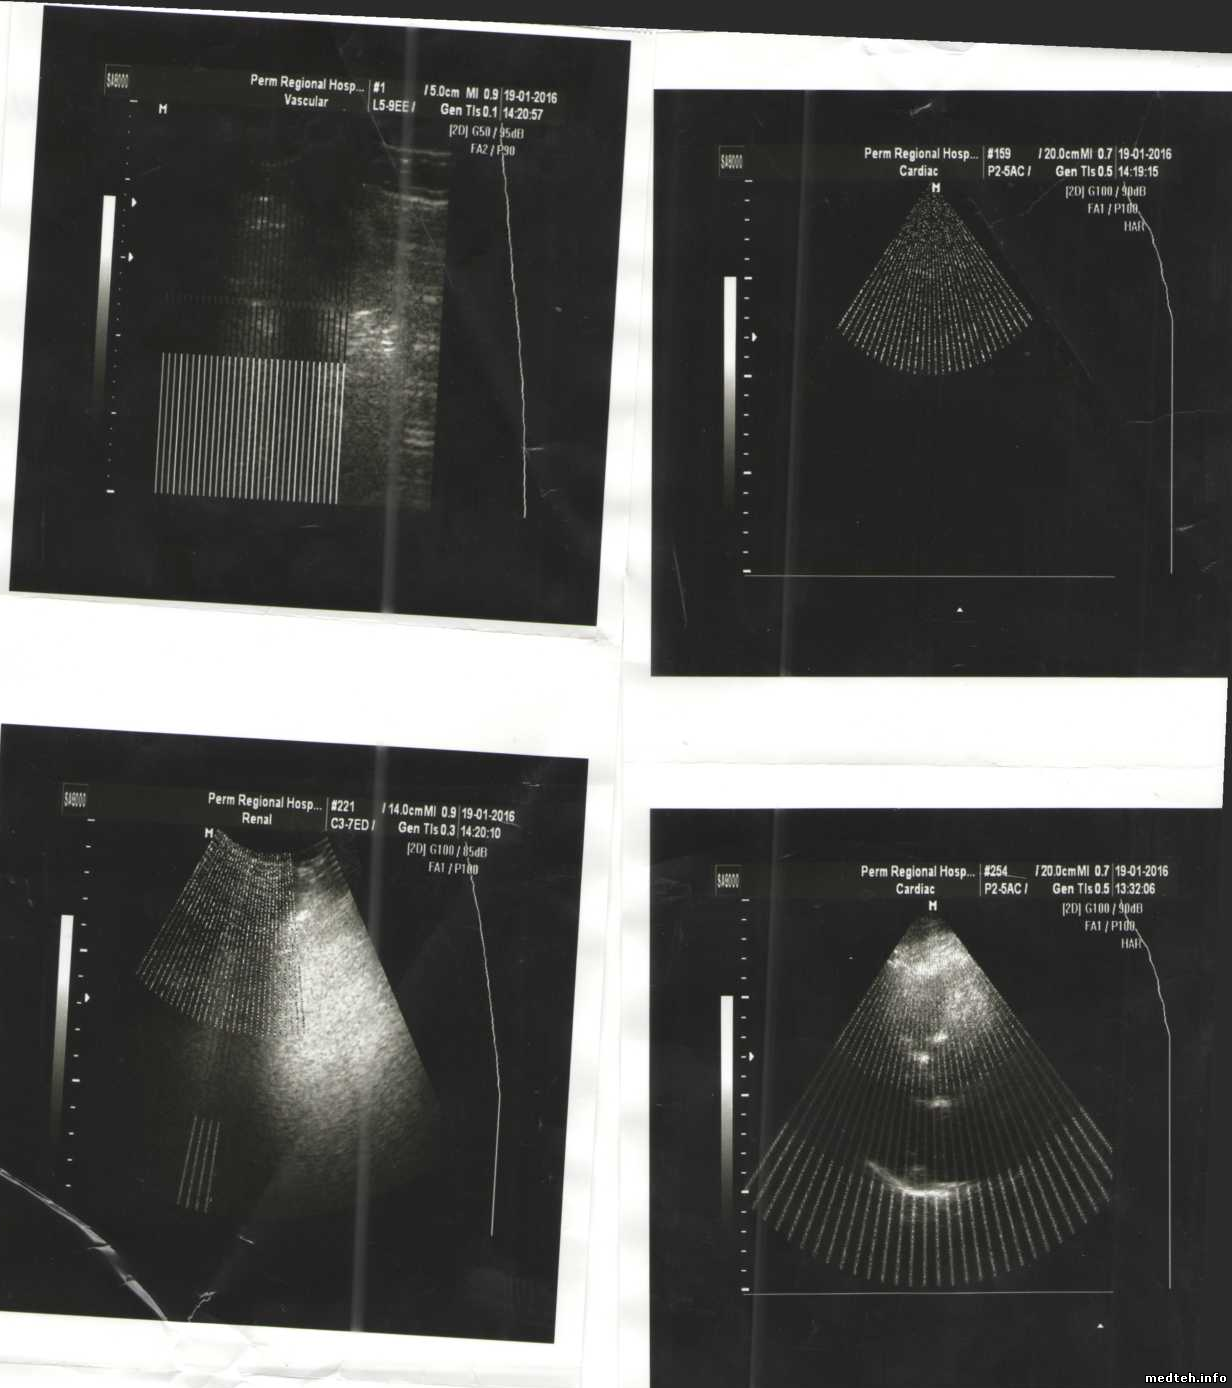

Ребят помогите с проблемой на УЗИ аппарате SA-8000 EX-Eхр-CW.

При включении загрузка ПО проходит на ура. После входа в программу сразу же появляются помехи в виде полос.

ДАЖЕ при отключенных датчиках ireful ireful ireful

Начнем с того, что это не помехи, а проблемы с формированием УЗ-кадра. Очень похоже на "холодную пайку"...